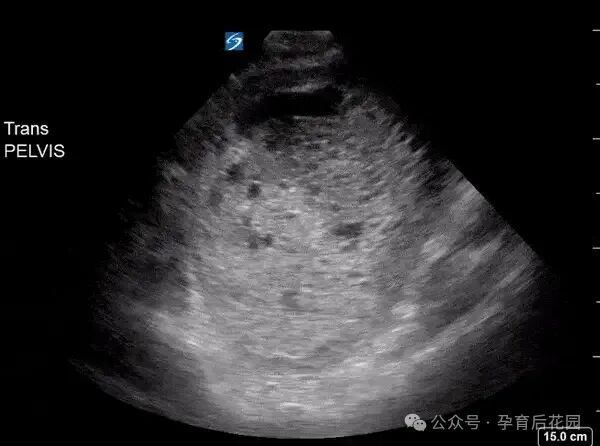

超声提示:宫腔内小囊性结构

▲图片来源于文献案例

看到 “囊性结构”“小” 这些字眼,大家肯定又犯嘀咕了,这到底怀没怀啊?其实,这说明很有可能怀孕了,但还得再观察一段时间才能确定。医生给出 “宫腔内小囊性结构” 这样比较保守的提示,除了正常宫内孕,还有两种不太好的可能:

(1)假孕囊

这种囊性结构不会随着孕周增加而长大,甚至还会缩小、消失,出现这种情况,宫外孕的可能性比较大。

(2)空孕囊

也就是说受精卵着床后发育不正常,还没形成胚胎就停止发育了。不管是哪种情况,都得持续随访观察。

无论哪种情况,都需要随访观察。